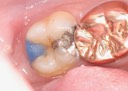

Ted Kanamori #14 pre-op

Ted Kanamori #14 amalgam removal

Ted Kanamori #14 prep